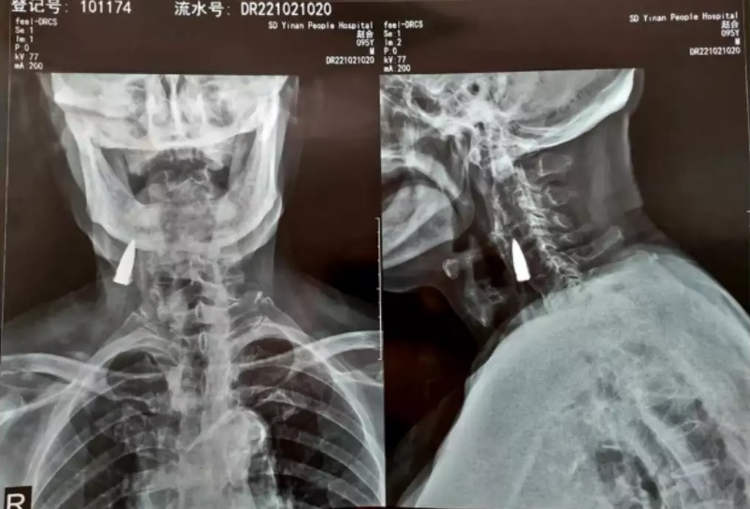

Para ser más exactos, Zhao He se dio cuenta del hallazgo tras acudir al hospital de Linyi, provincia de Shandong, para un examen físico el pasado viernes 21 de octubre. Allí, los médicos encontraron una bala clavada en su cuello cuando le realizaron una radiografía.

De hecho, Zhao estima que la bala podría haber estado en su cuello desde 1944, cuando le alcanzó la bala mientras cruzaba el río. La bala supuestamente entró por el lado izquierdo de la nariz, perforándole la mandíbula superior y arrancándole los dientes antes de alojarse en su cuello.